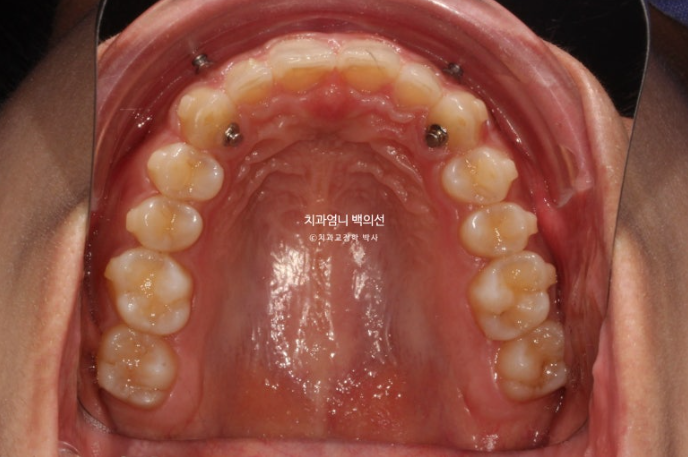

24년 3월 잇몸성형을 위해 오신 분입니다.

위 앞니 4개가 전반적으로 짧은 편이고 웃을 때 잇몸이 많이 보이는 거미스마일이 있습니다.

잇몸성형으로 거미스마일을 어느정도는 해결할 수 있지만 앞니가 뒤로 쓰러진 옥니이고 깊게 물리는 과개교합도 있고 앞니 사이도 벌어져 있어서 교정을 권유드렸습니다.

어금니교합은 좋습니다.

위 앞니가 아래 앞니를 깊게 덮어 아래앞니가 전혀 보이지 않는 정도의 심한 과개교합입니다.

위 앞니는 정상각도보다 뒤로 쓰러진 옥니입니다

앞니 사이사이에 벌어진 틈도 있습니다.

24.03

어금니 교합이 좋아 인비절라인 라이트 권유드렸고, 대신 미니스크류를 심고 고무줄을 걸어 길지 않은 기간에 과개교합과 거미스마일을 확실히 개선하기로 했습니다.